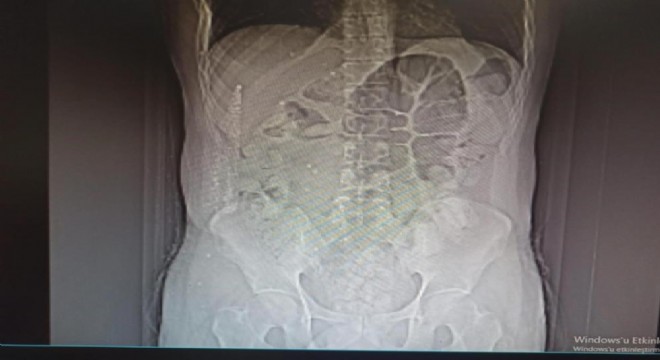

Midesinden 711 gram uyuşturucu çıktı

Erzincan polisinin uyuşturucu madde kuryeliği yapan şahıslara yönelik düzenlediği operasyonda, uyuşturucuyu midesine gizleyen İran uyruklu 1 kişi tutuklandı. 711,86 gram Afyon sakızı ele geçirildi.

İl Emniyet Müdürlüğü Narkotik Suçlarla Mücadele Şube Müdürlüğü ile Kaçakçılık ve Organize Suçlarla Mücadele Şube Müdürlüğü ekiplerince yapılan ortak çalışmada; uygulama noktasında durdurulan, İran otobüsünde yolcu olarak bulunan İran uyruklu şüpheli M.K. (31) isimli kişiye yapılan tomografi çekiminde mide ve bağırsak kısmında uyuşturucu olabileceğini değerlendirilen çok sayıda yabancı cismin olduğu tespit edildi.

Yapılan tetkikler neticesinde M.K.’nın midesinden 64 parça halinde 711,86 gr gelen Afyon Sakızı ele geçirildi.